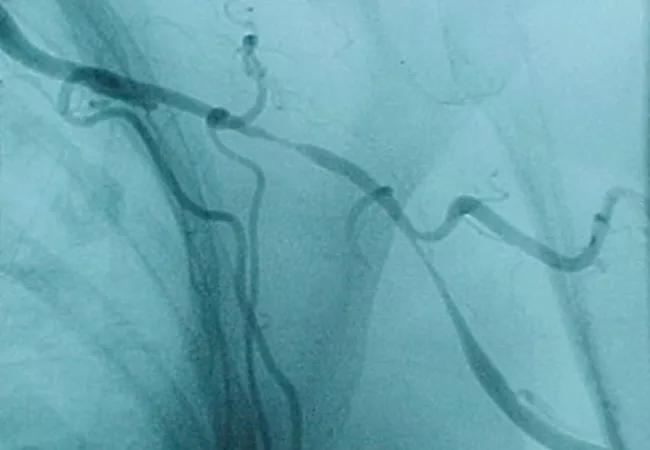

Histopathology of temporal artery of the nine patients with a final diagnosis of biopsy-proven GCA revealed arteritis, with mononuclear cell inflammatory infiltrates localized to the media and adventitia, varying amounts of intimal proliferation and fibrinoid necrosis, and fragmentation of the internal elastic lamina.

All biopsies from biopsy-negative patients with clinically positive GCA, revealed arteriosclerosis, with intimal thickening and rare, focal calcification; 20 of 23 control TA without GCA also shared these findings. Tthree TA from controls were normal.